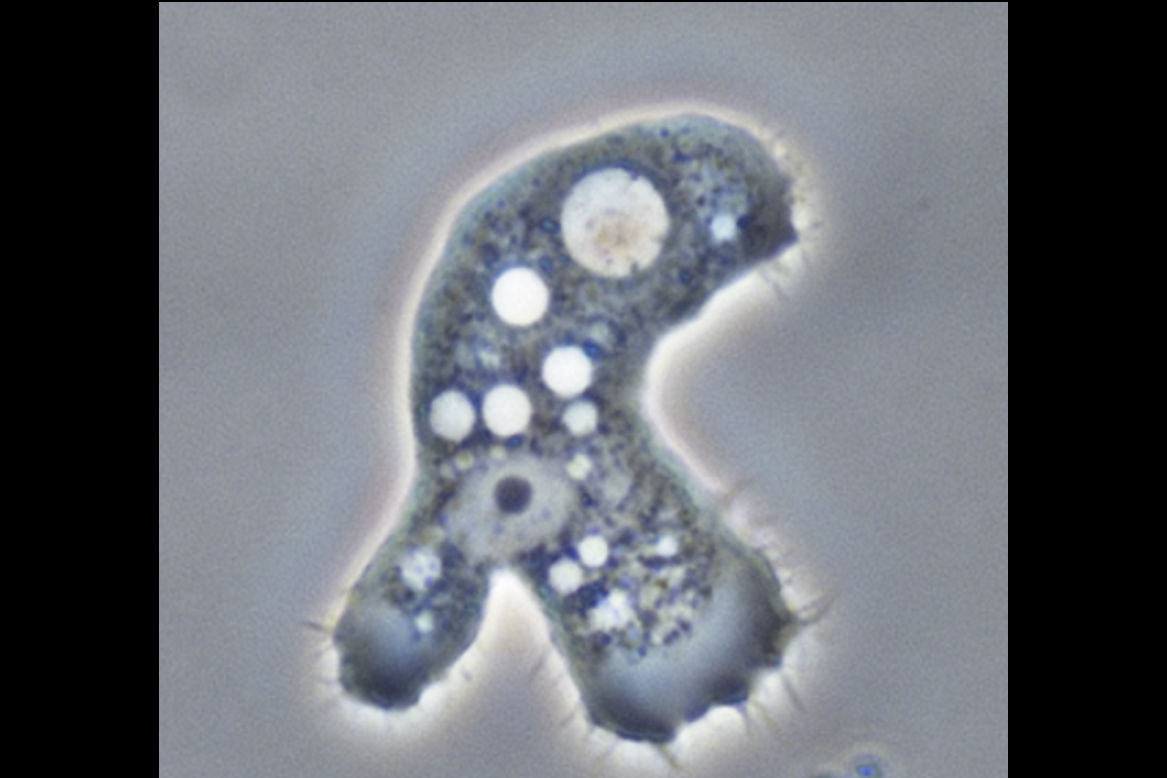

The organism’s biology makes the condition difficult to treat. A key feature enabling this protozoan’s therapeutic resistance is the ability to transition between two forms: the active ‘trophozoite’ form (tropho is Greek for ‘food’—it marks its feeding, growing and invasive phase) that infects tissues; and when the nutrients disappear or drugs are introduced, a dormant ‘cyst’ form. Under unfavorable conditions, trophozoites encase themselves in cysts, double-walled structures that are extremely resistant to external attacks. This capacity for encystment contributes to both treatment failure and disease recurrence. Clinicians often observe that inflammation and tissue damage continue even after the pathogen load (number of pathogens present at the site of infection) has been reduced or the infected tissue has been removed. So, what drives the damage in the cornea - pathogen load or the hosts' immune response?

Photo credit: Acanthamoeba keratitis, Lorenzo-Morales, Khan, Walochnik, CC BY 4.0